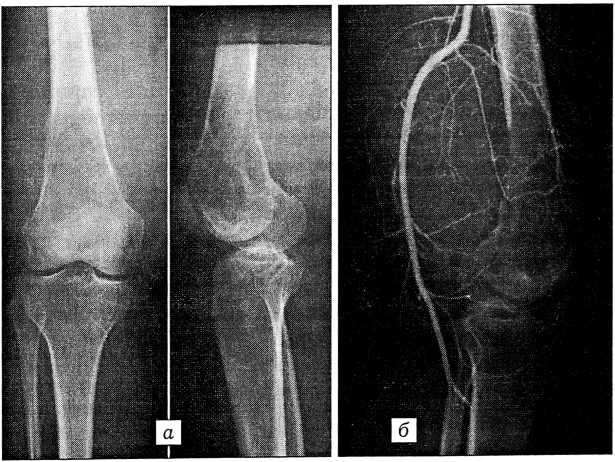

При поступлении в нижней трети правого бедра определяется опухолевое образование размером 16x12 см, распространяющееся в подколенную область. Голень резко отечна. На рентгенограммах (рис. 1) — вздутие дистального метаэпифиза бедренной кости крупноячеистого характера, деструкция кости, периостальная реакция по ее переднему краю, патологический перелом. Мягкие ткани уплотнены, коленный сустав не изменен. Произведена трепанобиопсия. Получено заключение (проф. Н.Н. Петровичев): в представленном материале содержатся кусочки опухоли, состоящие преимущественно из межуточного компонента (коллагеновые волокна) и фибробластоподобных клеток; материала мало для уточнения как гистогенеза, так и характера опухоли; в первую очередь следует думать о высокодифференцированной фибросаркоме или десмопластической фиброме.

Рис. 1. Рентгенограммы больной Ц. в прямой и боковой проекциях (а) и ангиограмма (б) до операции.